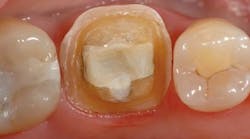

A 50-year-old female patient presented following a distobuccal fracture of tooth No. 19 (figure 2). After examination and discussion, a full-coverage restoration was planned. Local anesthesia was achieved with one cartridge of 4% Articadent Dental and epinephrine 1:100,000 (Dentsply Sirona). The tooth was carefully prepared to meet the reduction guidelines for Celtra Duo. In this case, a 1 mm circumferential shoulder was prepared with axial wall and occlusal reductions of 1.0–1.5 mm and 1.5 mm, respectively (figure 3).

Figure 2: Preoperative view of tooth No. 19 showing a distobuccal fracture necessitating a full-coverage restoration.

Figure 3: Final preparation of tooth No. 19.

The preparation design included a minimum of 1 mm reduction for a shoulder finish line, 1.0–1.5 mm reduction for the axial walls, and at least 1.5 mm reduction across the occlusal surface.